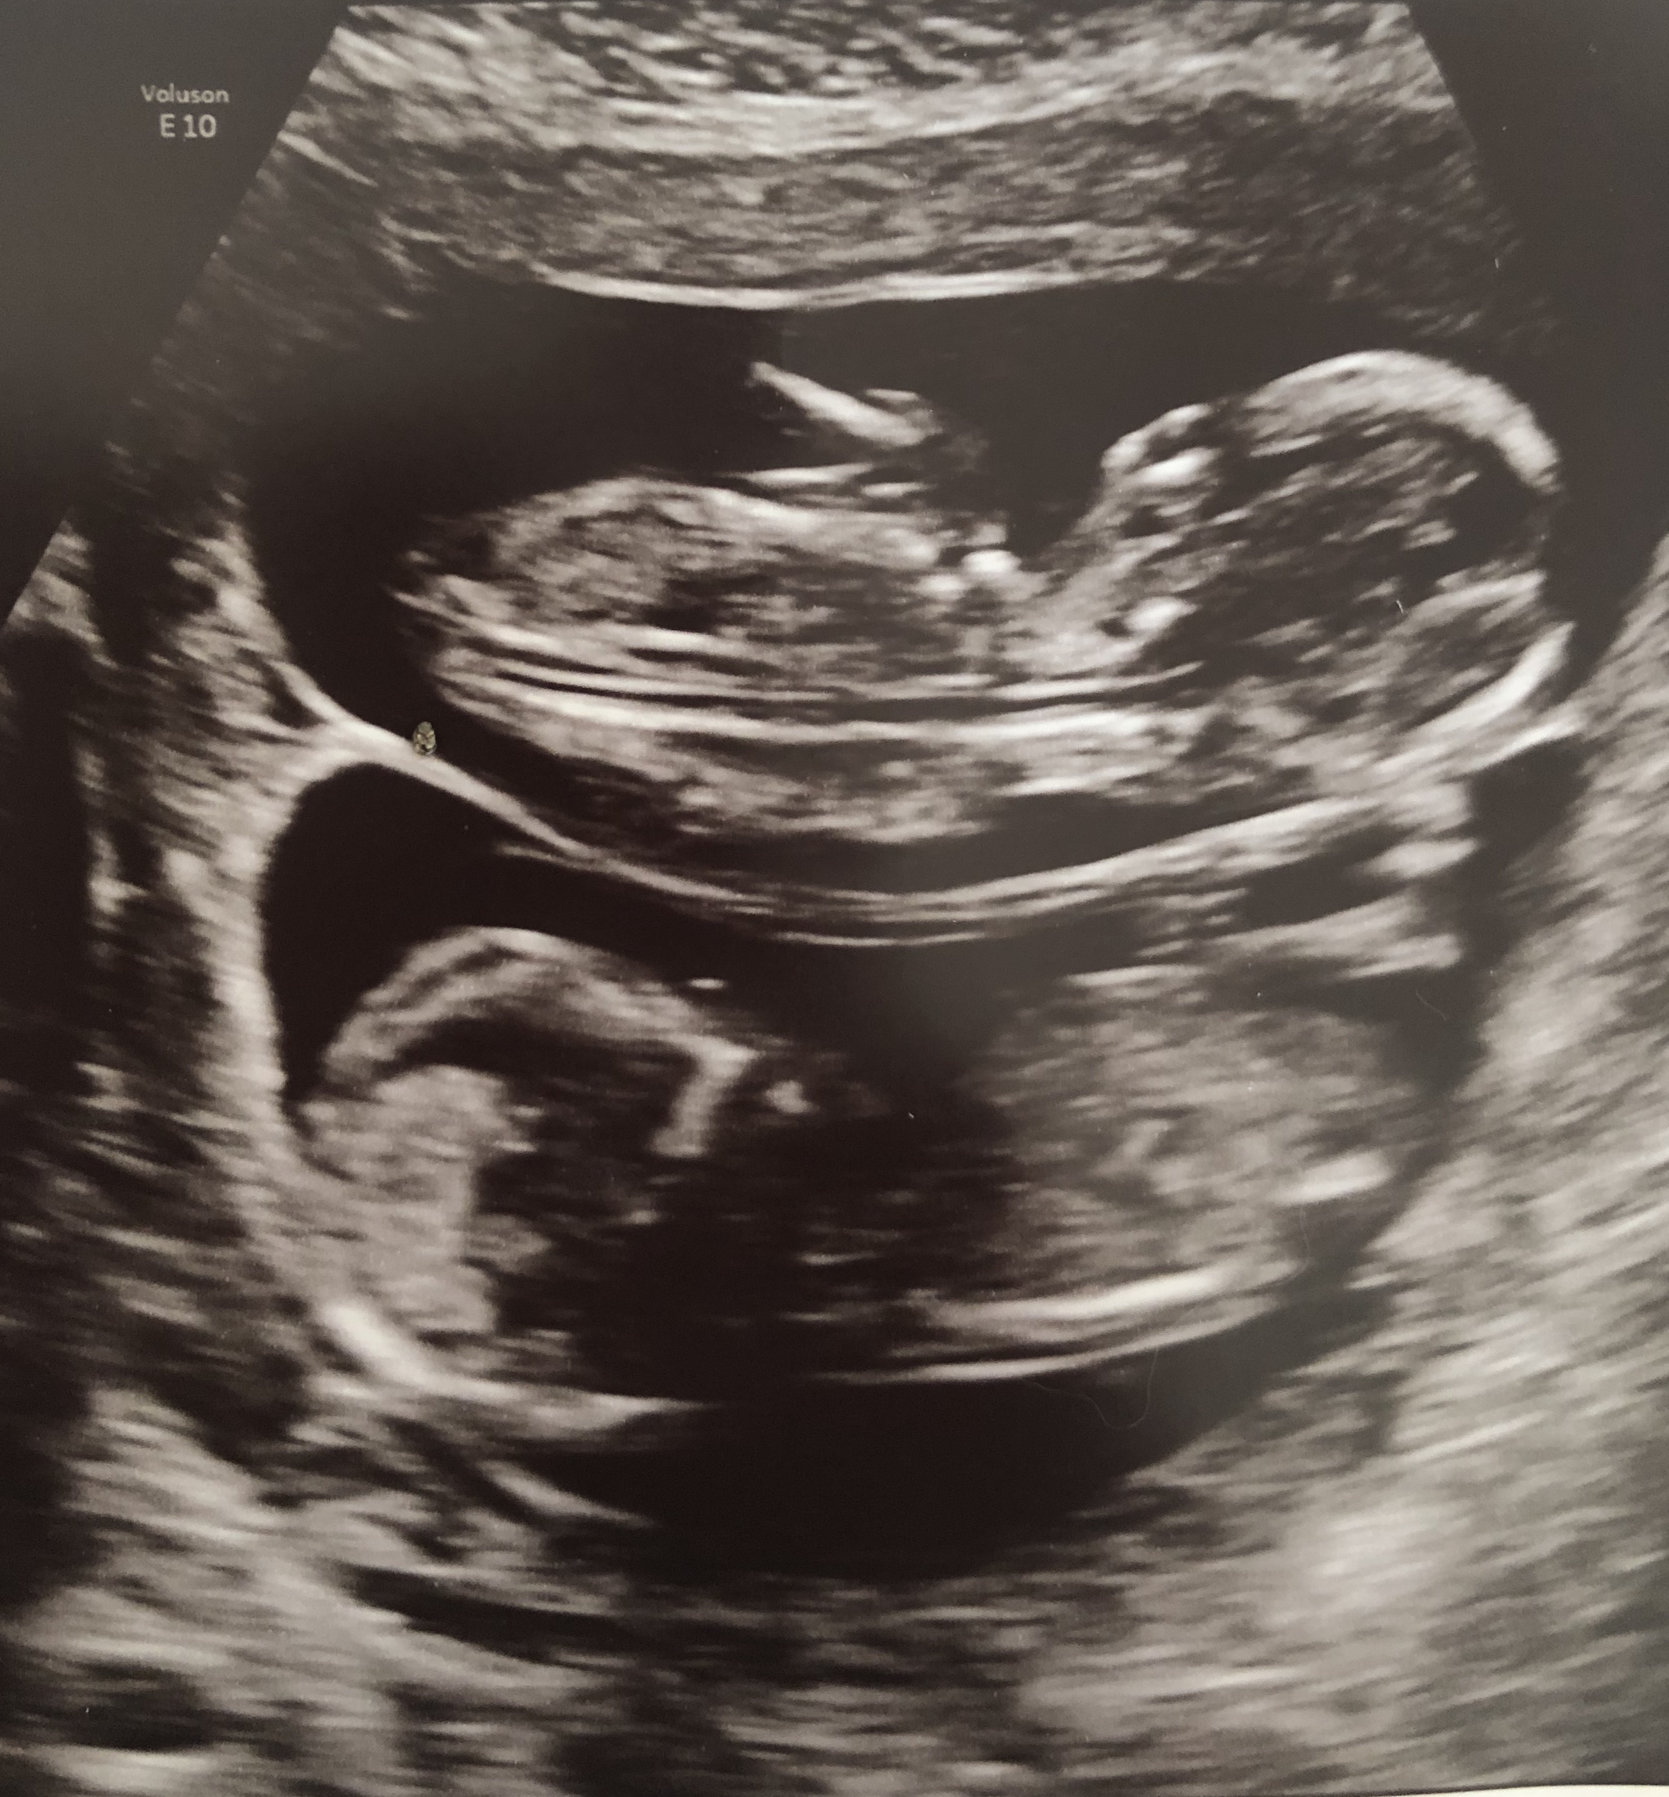

Shots from our NT scan at 12 weeks + 3 days. Measuring right on track, and the tech thought Baby B looked like a boy!